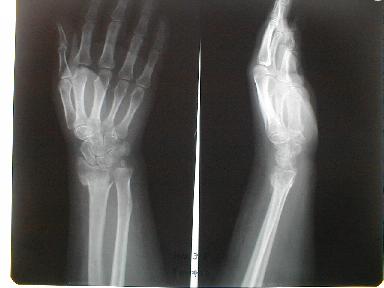

3月6日 受傷30日目

手関節背屈でレントゲン撮影時した為に骨折部がズレて見える